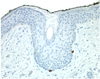

Q

Identify

Identify

Identify